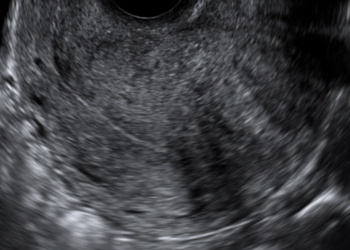

How To Do Febbraio 2024: Istmocele

Cari soci, questo mese un nuovo video "How to do", dedicato allo studio ecografico dell'istmocele Grazie a Daniela Giuliani! Il...